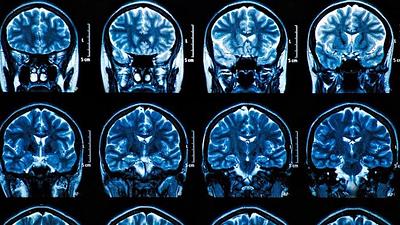

Hormônio produzido pelos músculos pode conter avanço do Alzheimer

Conduzido por pesquisadores da UFRJ, estudo mostra que atividades físicas podem prevenir perda de memória causada pela doença em roedores. Hormônio irisina seria responsável por esse efeito.